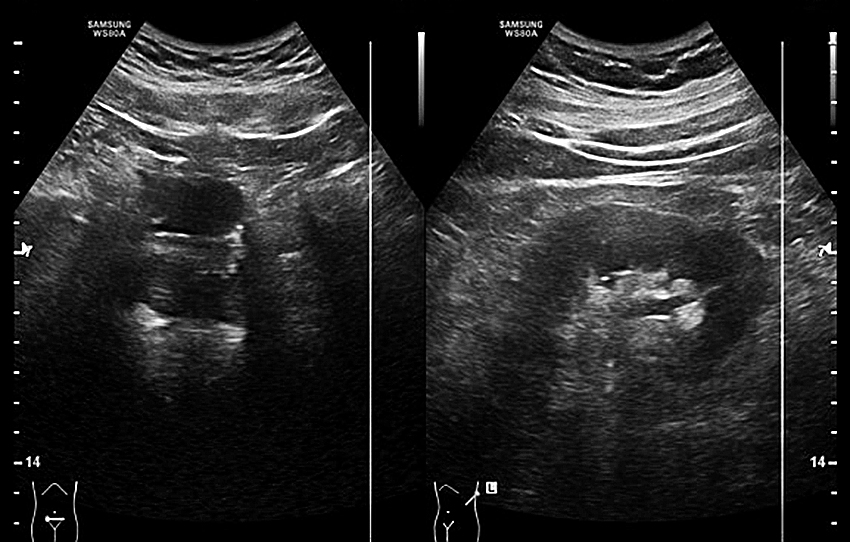

Durch ein low-dose- oder Nativ-CT vom Abdomen können neben den Kelchsteinen die Harnleitersteine sehr sicher nachgewiesen oder ausgeschlossen werden. Durch die immer besser werdenden Sonographiegeräte lassen sich allerdings auch bei geringen Aufweitungen die Ursachen der Obstruktionsstörung des oberen Harntraktes finden. Die Kindernephrologen und Kinderradiologen versuchen schon seit längerem, auf radiologische Diagnostik am oberen Harntrakt zu verzichten, da hier die Strahlenbelastung noch mehr Bedeutung hat. Auch für die Erwachsenenurologie sollte die Reduzierung der Strahlenbelastung bei der Abklärung der Harnstauungsniere ein Argument sein.

Bei den distal-prävesikalen Steinen hat der transrektale Ultraschall schon längere Zeit seine Bedeutung gefunden, allerdings nur bei wenigen Untersuchern. Bei Frauen eignet sich dazu der transvaginale Schall, der den Harnleiter bis zur Gefäßkreuzung verfolgen und den erweiterten Harnleiter komplett mit dem transabdominalen Schall auf eine Steinobstruktion untersuchen lässt. In der gynäkologischen Abteilung steht mir seit 2/2017 ein high-end-Sonogerät der Fa. Samsung WS80A zur Verfügung.

Bei den 295 stationären Patienten mit Nierenkoliken hatten 111 Patienten einen proximalen Stein, bei 184 Patienten wurde der Stein distal der Gefäßkreuzung gesichert. Bei den prävesikalen Steinen konnte in der transrektalen Sonographie der Stein bei den Männern in den letzten 3,5 cm sicher gesehen, in der vaginalen Sonographie der Harnleiter mit dem Stein teilweise bis zu den iliakalen Gefäßen verfolgt werden.

Bei den 111 Patienten mit proximalen Steinen konnten die Steine bei 102 Patienten (92 %) auch im Ultraschall gesehen werden. Bei 59 Patienten (53 %) war für die Steinsicherung kein CT angefordert worden. Bei den 184 Patienten mit distalen Harnleitersteinen wurde der Stein bei 171 Fällen (93 %) in der transrektalen/transvaginalen Sonographie verifiziert, bei 123 Patienten (66 %) wurde auf eine CT-US verzichtet. Fornixrupturen konnten bei den letzten 50 Patienten zu 22 % durch high-end-Geräte gesehen werden, immer ohne klinische Konsequenz; bei 6 Patienten wurde bei der Aufnahmeuntersuchung eine Urosepsis erkannt und durch die alleinige sonographische Steinsichtung rasch einer endoskopischen Steinsanierung zugeführt.